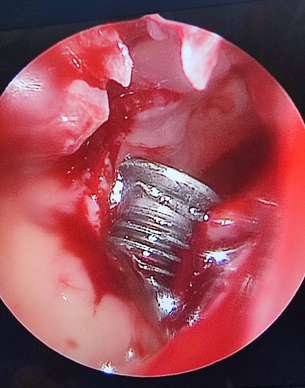

Клинический пример. Раненый П. с огнестрельным слепым ранением средней зоны лица и инородным телом клиновидной пазухи. По результатам КЛКТ головы выявлено инородное тело металлической плотности в левой половине клиновидной пазухи. Под общей анестезией эндоназальным доступом с помощью эндовидеоскопической техники через переднюю стенку выполнено удаление инородного тела. Операция прошла без осложнений.

Эндоскопическая картина при удалении огнестрельного инородного тела из клиновидной пазухи через переднюю стенку.